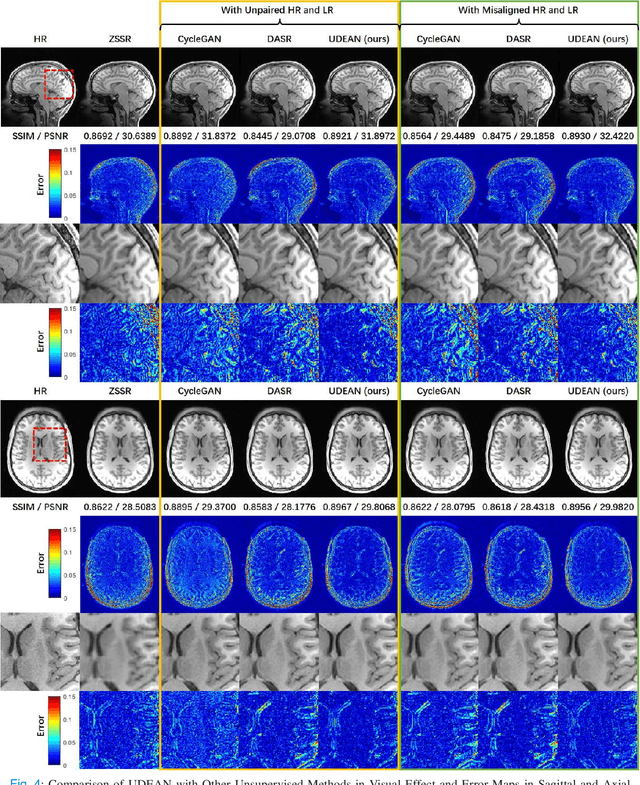

Abstract:High-resolution (HR) MRI is critical in assisting the doctor's diagnosis and image-guided treatment, but is hard to obtain in a clinical setting due to long acquisition time. Therefore, the research community investigated deep learning-based super-resolution (SR) technology to reconstruct HR MRI images with shortened acquisition time. However, training such neural networks usually requires paired HR and low-resolution (LR) in-vivo images, which are difficult to acquire due to patient movement during and between the image acquisition. Rigid movements of hard tissues can be corrected with image-registration, whereas the alignment of deformed soft tissues is challenging, making it impractical to train the neural network with such authentic HR and LR image pairs. Therefore, most of the previous studies proposed SR reconstruction by employing authentic HR images and synthetic LR images downsampled from the HR images, yet the difference in degradation representations between synthetic and authentic LR images suppresses the performance of SR reconstruction from authentic LR images. To mitigate the aforementioned problems, we propose a novel Unsupervised DEgradation Adaptation Network (UDEAN). Our model consists of two components: the degradation learning network and the SR reconstruction network. The degradation learning network downsamples the HR images by addressing the degradation representation of the misaligned or unpaired LR images, and the SR reconstruction network learns the mapping from the downsampled HR images to their original HR images. As a result, the SR reconstruction network can generate SR images from the LR images and achieve comparable quality to the HR images. Experimental results show that our method outperforms the state-of-the-art models and can potentially be applied in real-world clinical settings.